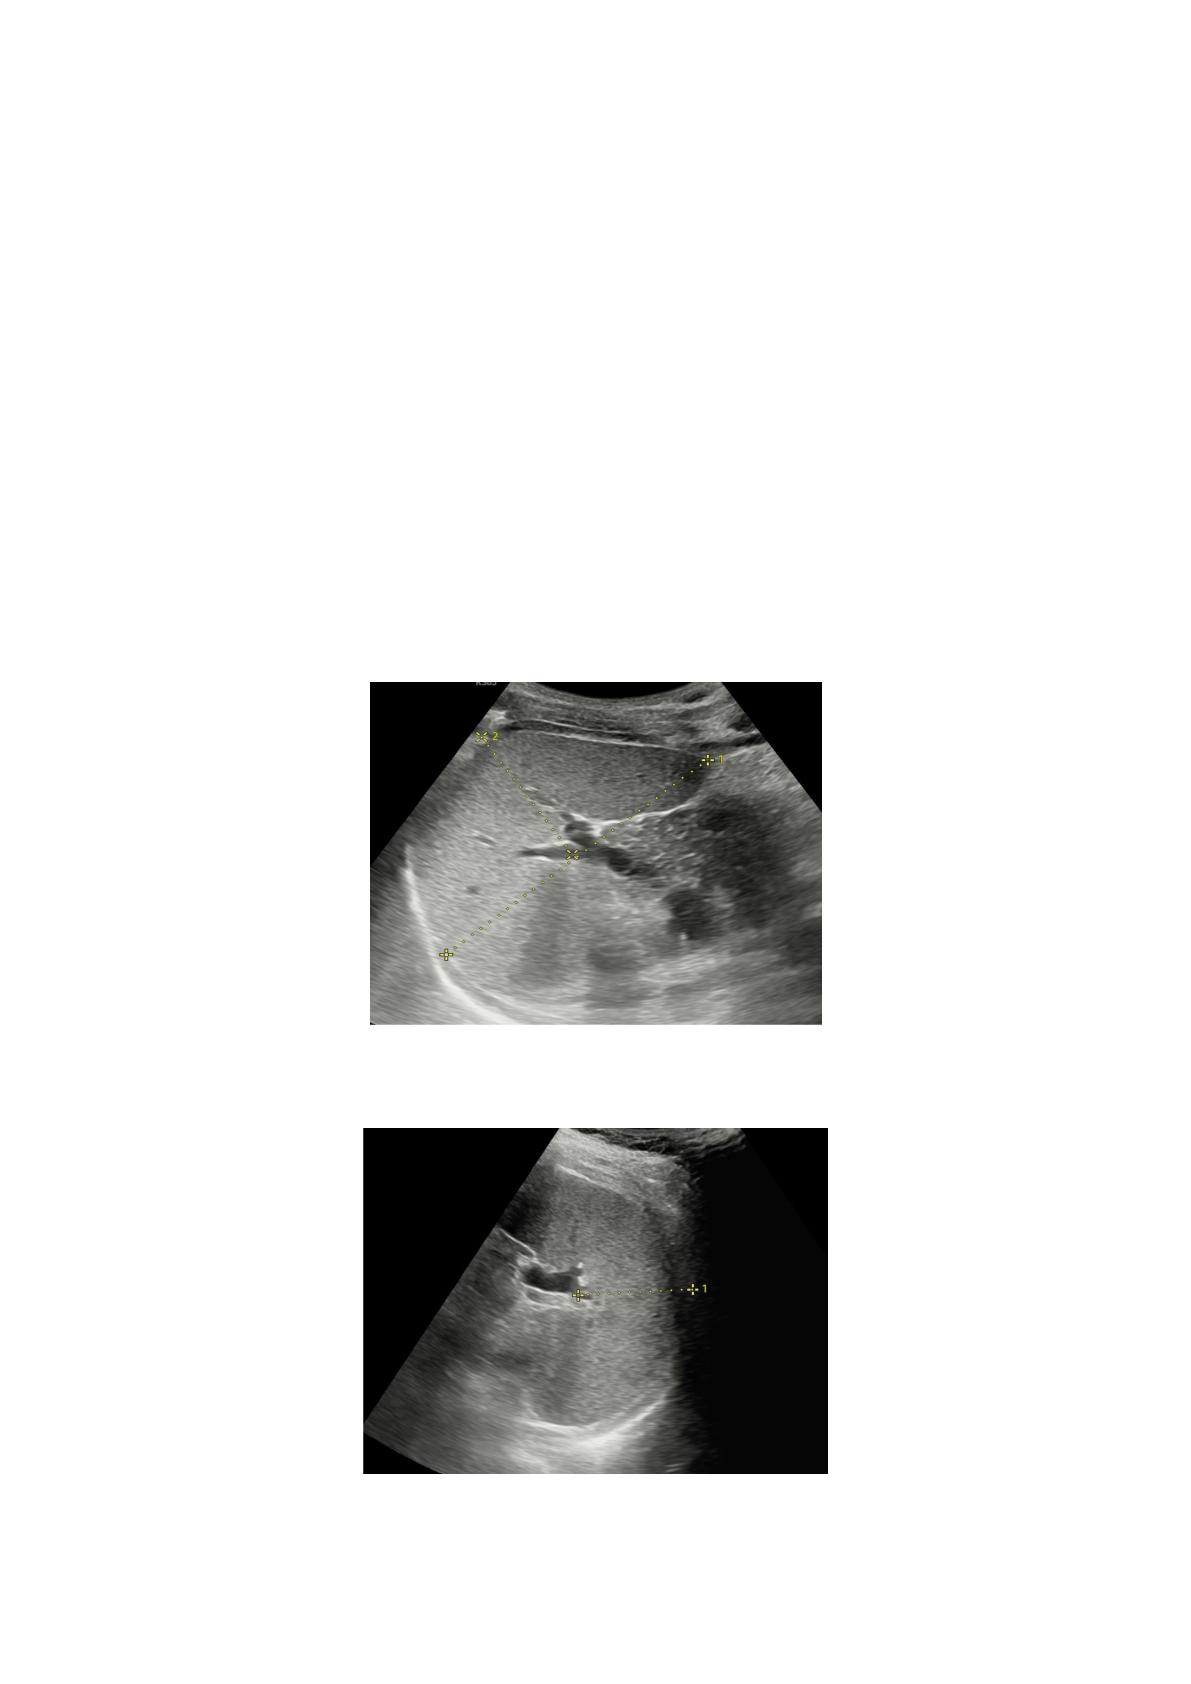

Français La différence entre les groupes d'IMC en termes de

valeurs LL était statistiquement significative (p = 0,000). Tous les

groupes d'IMC différaient significativement les uns des autres en

termes de valeurs LL (p = 0,000). La valeur LL moyenne du groupe en

insuffisance pondérale était la plus basse, et la valeur LL moyenne du

groupe obèse était la plus élevée. Il a été observé qu'une

augmentation des valeurs d'IMC entraînait une augmentation des

valeurs LL. La différence entre les groupes d'IMC en termes de valeur

LD était statistiquement significative (p = 0,000). La différence entre

les valeurs LD des groupes en insuffisance pondérale et d'IMC normal

n'était pas statistiquement significative (p = 0,079). D'autre part, la

différence entre les valeurs LD des autres groupes d'IMC était

statistiquement significative (p = 0,000). La valeur LD moyenne la plus

élevée a été observée dans le groupe obèse.

La différence entre les groupes d'IMC en termes de valeur SL

n'était pas statistiquement significative (p = 0,583). Une corrélation

significative a été trouvée entre la valeur ST et l'IMC (p = 0,016).